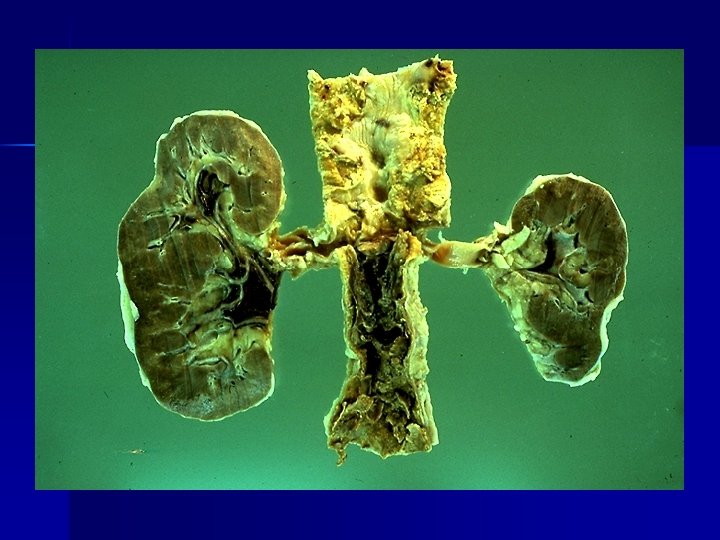

Causas: - Isquemia: Disminución de oxigeno, necrosis isquémica - infartos- oclusión vascular. - Inflamación crónica (infecciones virales o bacterianas) atrofia. - Disminución de la actividad del músculo esquelético: reposo prolongado, inanición o nutrición inadecuada. - Interrupción de las señales tróficas (denervación: polio) - Interrupción de las señales hormonales (ablación glandular)

- Demanda funcional aumentada. Músculos, hipertrofía cardiaca por hipertensión, hepatocitos (aumento de REL por estímulo de fenobarbital y drogas hipolipemiantes)- hepatomegalia fisiológica - Hipertrofia del riñón contralateral. - Más frecuentes en tejidos pemanentes y estables.